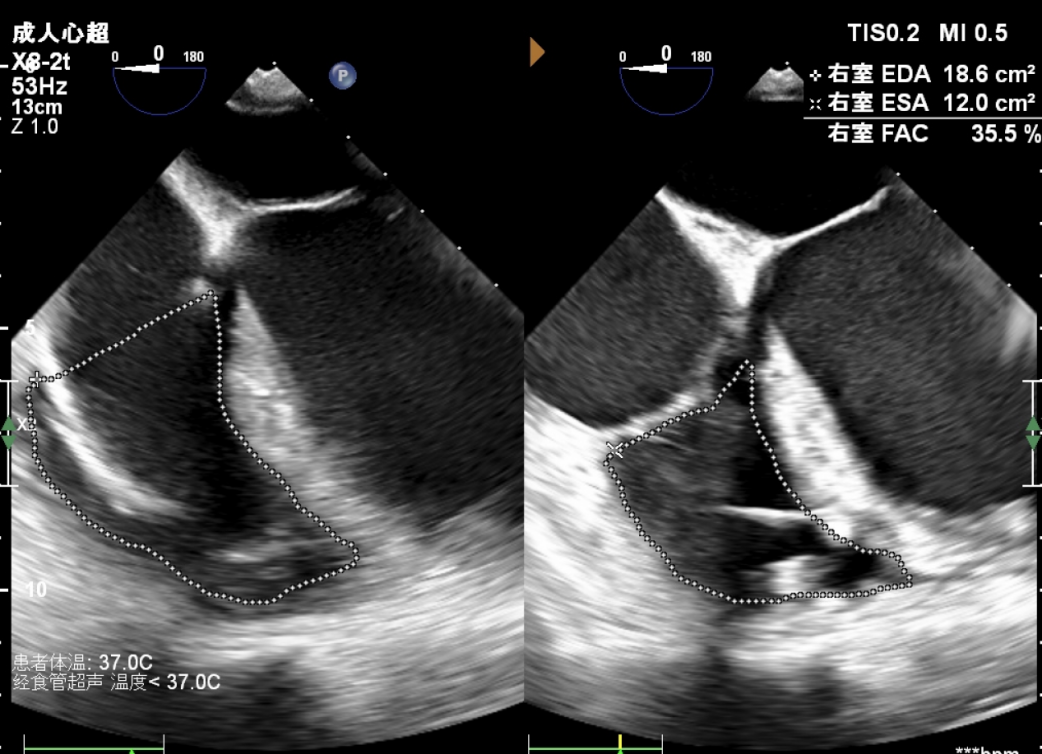

心脏超声检查进一步揭示患者病情的严峻性:ECMO辅助状态下室壁运动功能欠协调、收缩功能显著减低,左心室舒张末期内径69mm,射血分数(EF)仅22%,三尖瓣TAPSE 12mm,右室FAC 30%,属于终末期心衰的极危重状态,常规药物治疗已无法逆转病情,患者生命如悬丝般脆弱。

术后床旁超声检查验证了手术效果:患者左心室负荷显著降低,血流动力学指标明显改善,生命体征逐步平稳,心衰症状得到根本性缓解,标志着此次阶梯式治疗圆满达成核心目标。